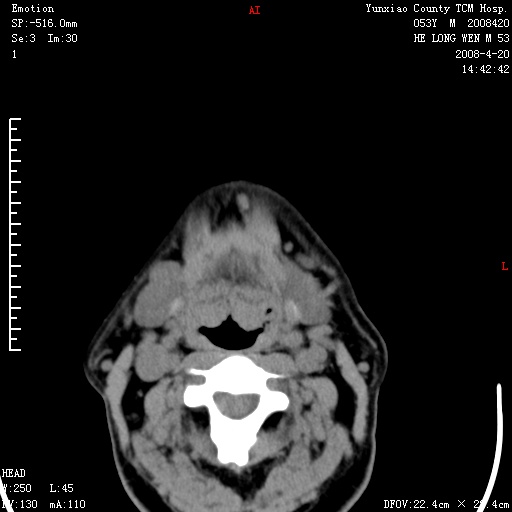

双侧扁桃体肿大:考虑化脓性扁桃体炎。

双侧扁桃体肿大 ,考虑扁桃体炎。

双侧扁桃体肿大,建议结合临床!

双侧扁桃体肿大 ,考虑扁桃体炎

能强化就强化,不能强化就喉镜检查。如怀疑扁桃体肿大,应再往上扫

应该有症状,体检此部位不是常规体检项目,支持双侧扁桃体肿大 ,考虑扁桃体炎,但还是强化一下吧。

双侧扁桃体肿大,考虑扁桃体炎,应做一下增强

显示部分为舌扁桃体,腭扁桃体未见显示。会厌显示欠规则,建议喉镜。